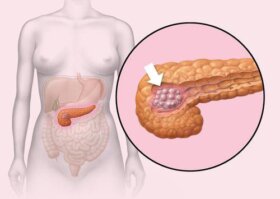

대부분은 췌장이 정확하게 우리 몸에서 어떤 기능을 하고, 어떻게 췌장 관련 문제들을 예방할 수 있는지에 대해서는 잘 모른다. 이 글에서는 췌장이 하는 일과 어떤 올바른 음식과 보충제를 섭취함으로서 균형을 유지하고, 췌장 건강을 개선할지에 관해서 자세히 알아보자. 췌장이 하는 일은? 췌장은…